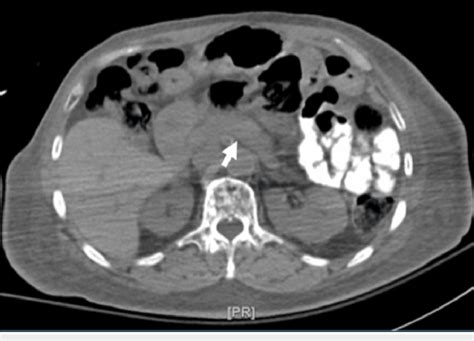

The abdomen normal png is a valuable resource for medical professionals and researchers, offering a detailed visual representation of the abdominal region in its typical, healthy state. This image is an essential tool for understanding the anatomy and structure of the abdomen, which is a complex and vital part of the human body. By examining the normal appearance of the abdomen, medical practitioners can identify any deviations or abnormalities that may indicate potential health issues.

One of the key benefits of using abdomen normal png images is the ability to compare and analyze them with other medical images. This comparison can help healthcare professionals identify subtle changes or anomalies that might be indicative of disease or injury. By having a baseline image of a healthy abdomen, medical experts can more effectively detect and diagnose a range of conditions, from gastrointestinal disorders to liver or kidney issues.